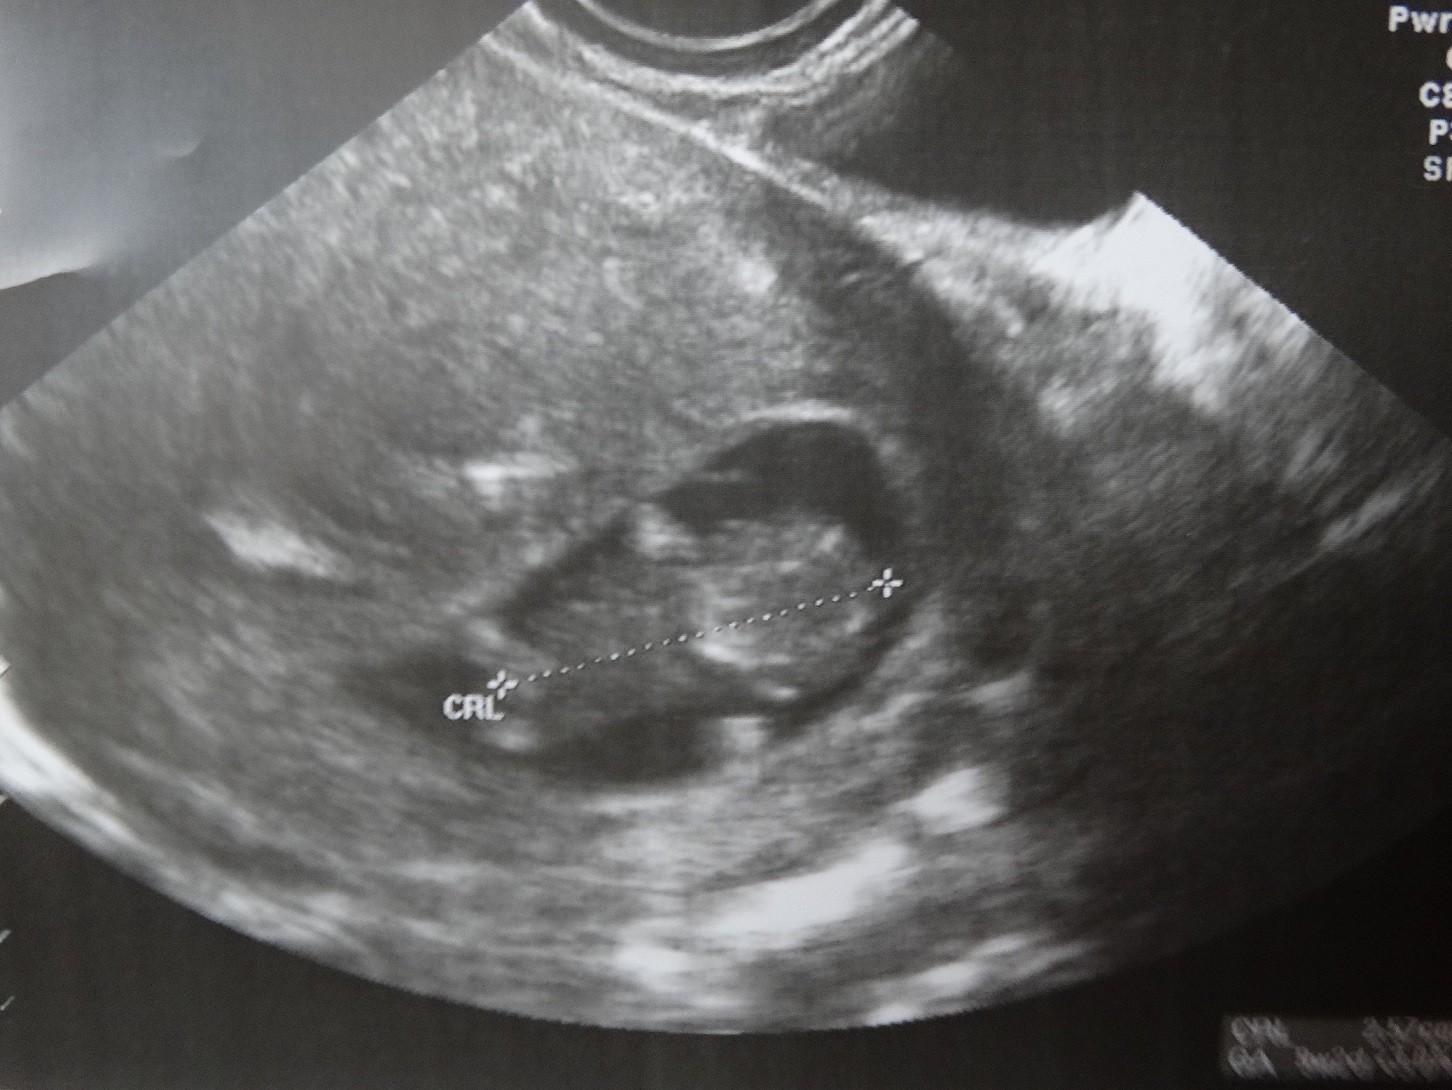

Dzisiejsze zdjęcie mojego maluszka :D

• DSC03124.JPG